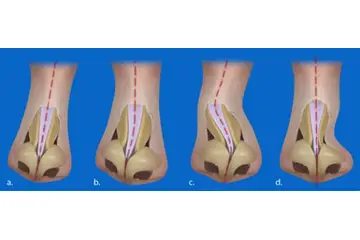

Burun Kıkırdak Eğriliği Belirtileri ve Tedavisi

Burun kıkırdak eğriliği, burun septumundaki bozuklukların neden olduğu rahatsız edici bir durumdur. Belirtileri arasında burun tıkanıklığı, baş ağrıları ve uyku apnesi yer alır. Tedavi seçenekleri, ilaçlardan cerrahi müdahalelere kadar değişir. Uzman görüşü, en uygun çözüm için önemlidir.

Burun Kıkırdak Eğriliği Belirtileri ve Tedavisi Burun kıkırdak eğriliği, burun septumunun (burun ortasındaki yapı) anormal bir şekilde eğrilmesi veya şekil bozukluğu olarak tanımlanabilir. Bu durum, bireylerin yaşam kalitesini etkileyen ve çeşitli sağlık sorunlarına yol açabilen önemli bir rahatsızlıktır. Burun kıkırdak eğriliği, genellikle doğuştan gelir, ancak travma veya yaralanmalar sonucu da gelişebilir. Burun Kıkırdak Eğriliğinin Belirtileri Burun kıkırdak eğriliği, birçok belirtiyle kendini gösterebilir. Bu belirtiler kişiden kişiye değişebilir, ancak genel olarak aşağıdaki semptomlar sıklıkla görülmektedir:

Tedavi Seçenekleri Burun kıkırdak eğriliği tedavisi, hastanın semptomlarına ve durumun ciddiyetine bağlı olarak değişiklik gösterir. Tedavi yöntemleri şunlardır: